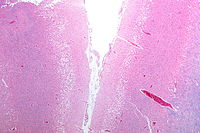

Micrograph showing cortical pseudolaminar necrosis, a finding seen in strokes on medical imaging and at autopsy. H&E-LFB stain.

Micrograph of the superficial cerebral cortex showing neuron loss and reactive astrocytes in a person that has had a stroke. H&E-LFB stain.